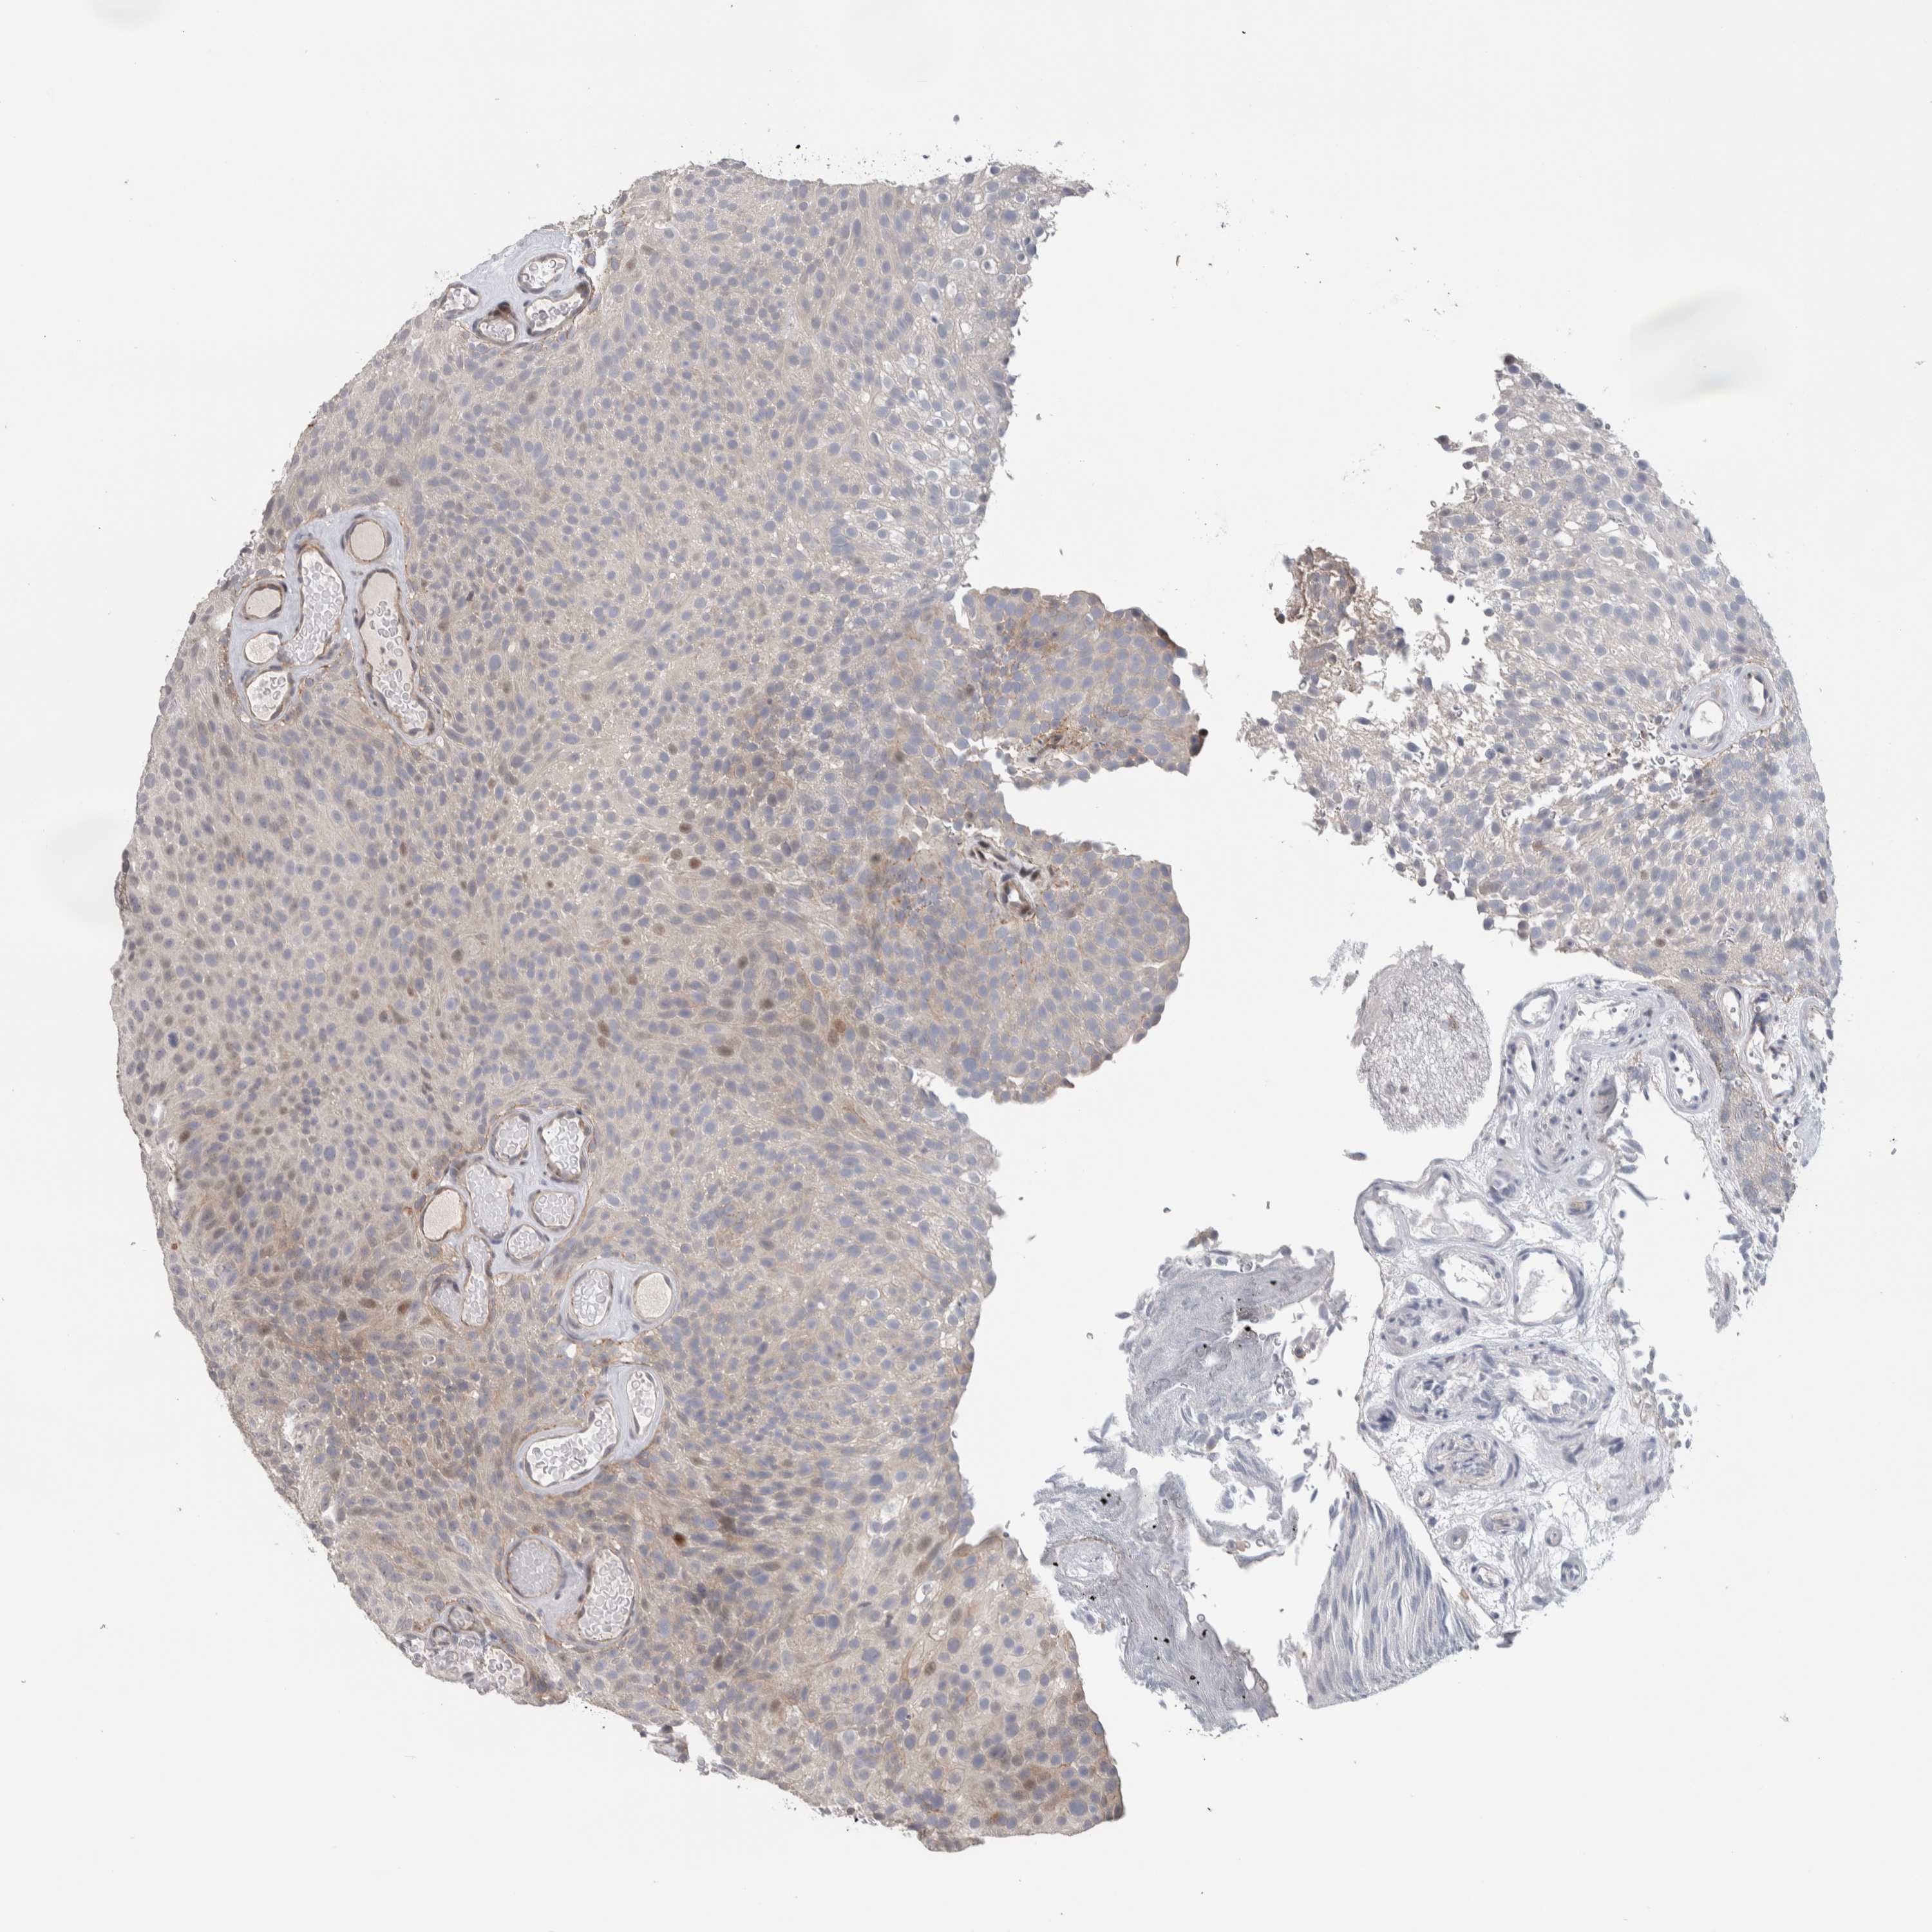

UROTHELIAL CANCER - Protein expressioni

A mouse-over function shows sample information and annotation data. Click on an image to view it in a full screen mode. Samples can be filtered based on level of antibody staining by selecting one or several of the following categories: high, medium, low and not detected. The assay and annotation is described here.

Note that samples used for immunohistochemistry by the Human Protein Atlas do not correspond to samples in the TCGA dataset.

Antibody stainingi

Antibody staining in the annotated cell types in the current human tissue is reported as not detected, low, medium, or high, based on conventional immunohistochemistry profiling in selected tissues. This score is based on the combination of the staining intensity and fraction of stained cells.

Each image is clickable and will lead to virtual microscopy that enables deeper exploration of all samples and also displays staining intensity scores, fraction scores and subcellular localization as well as patient and tissue information for each sample.

Antibody HPA009040

Antibody HPA024566

Staining

High

Medium

Low

Not detected

Intensity

Strong

Moderate

Weak

Negative

Quantity

>75%

75%-25%

<25%

None

Location

Nuclear

Cytoplasmic/membranous

Cytoplasmic/membranous,nuclear

Urothelial carcinoma, High grade

Urothelial carcinoma, Low grade